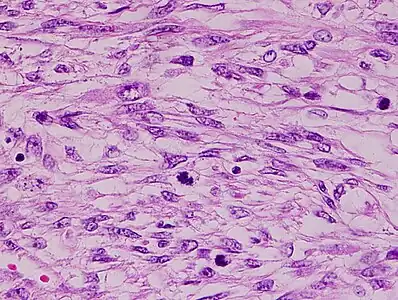

The tumors are usually hemorrhagic and soft and microscopically marked by pleomorphism, abundant (15–30 per 10 high-power fields) abnormal mitotic figures, and coagulative tumor cell necrosis. The differential diagnosis, which includes spindle cell carcinoma, spindle cell melanoma, fibrosarcoma, malignant peripheral nerve sheath tumor and even biphenotypic sinonasal sarcoma, is wide.

Histopathology of leiomyosarcoma shows variable atypia, often with cytoplasmic vacuoles at both ends of nuclei, and frequent mitoses.[11]

Diagnosis of LMS is made by performing a soft-tissue biopsy and examining its histopathology.